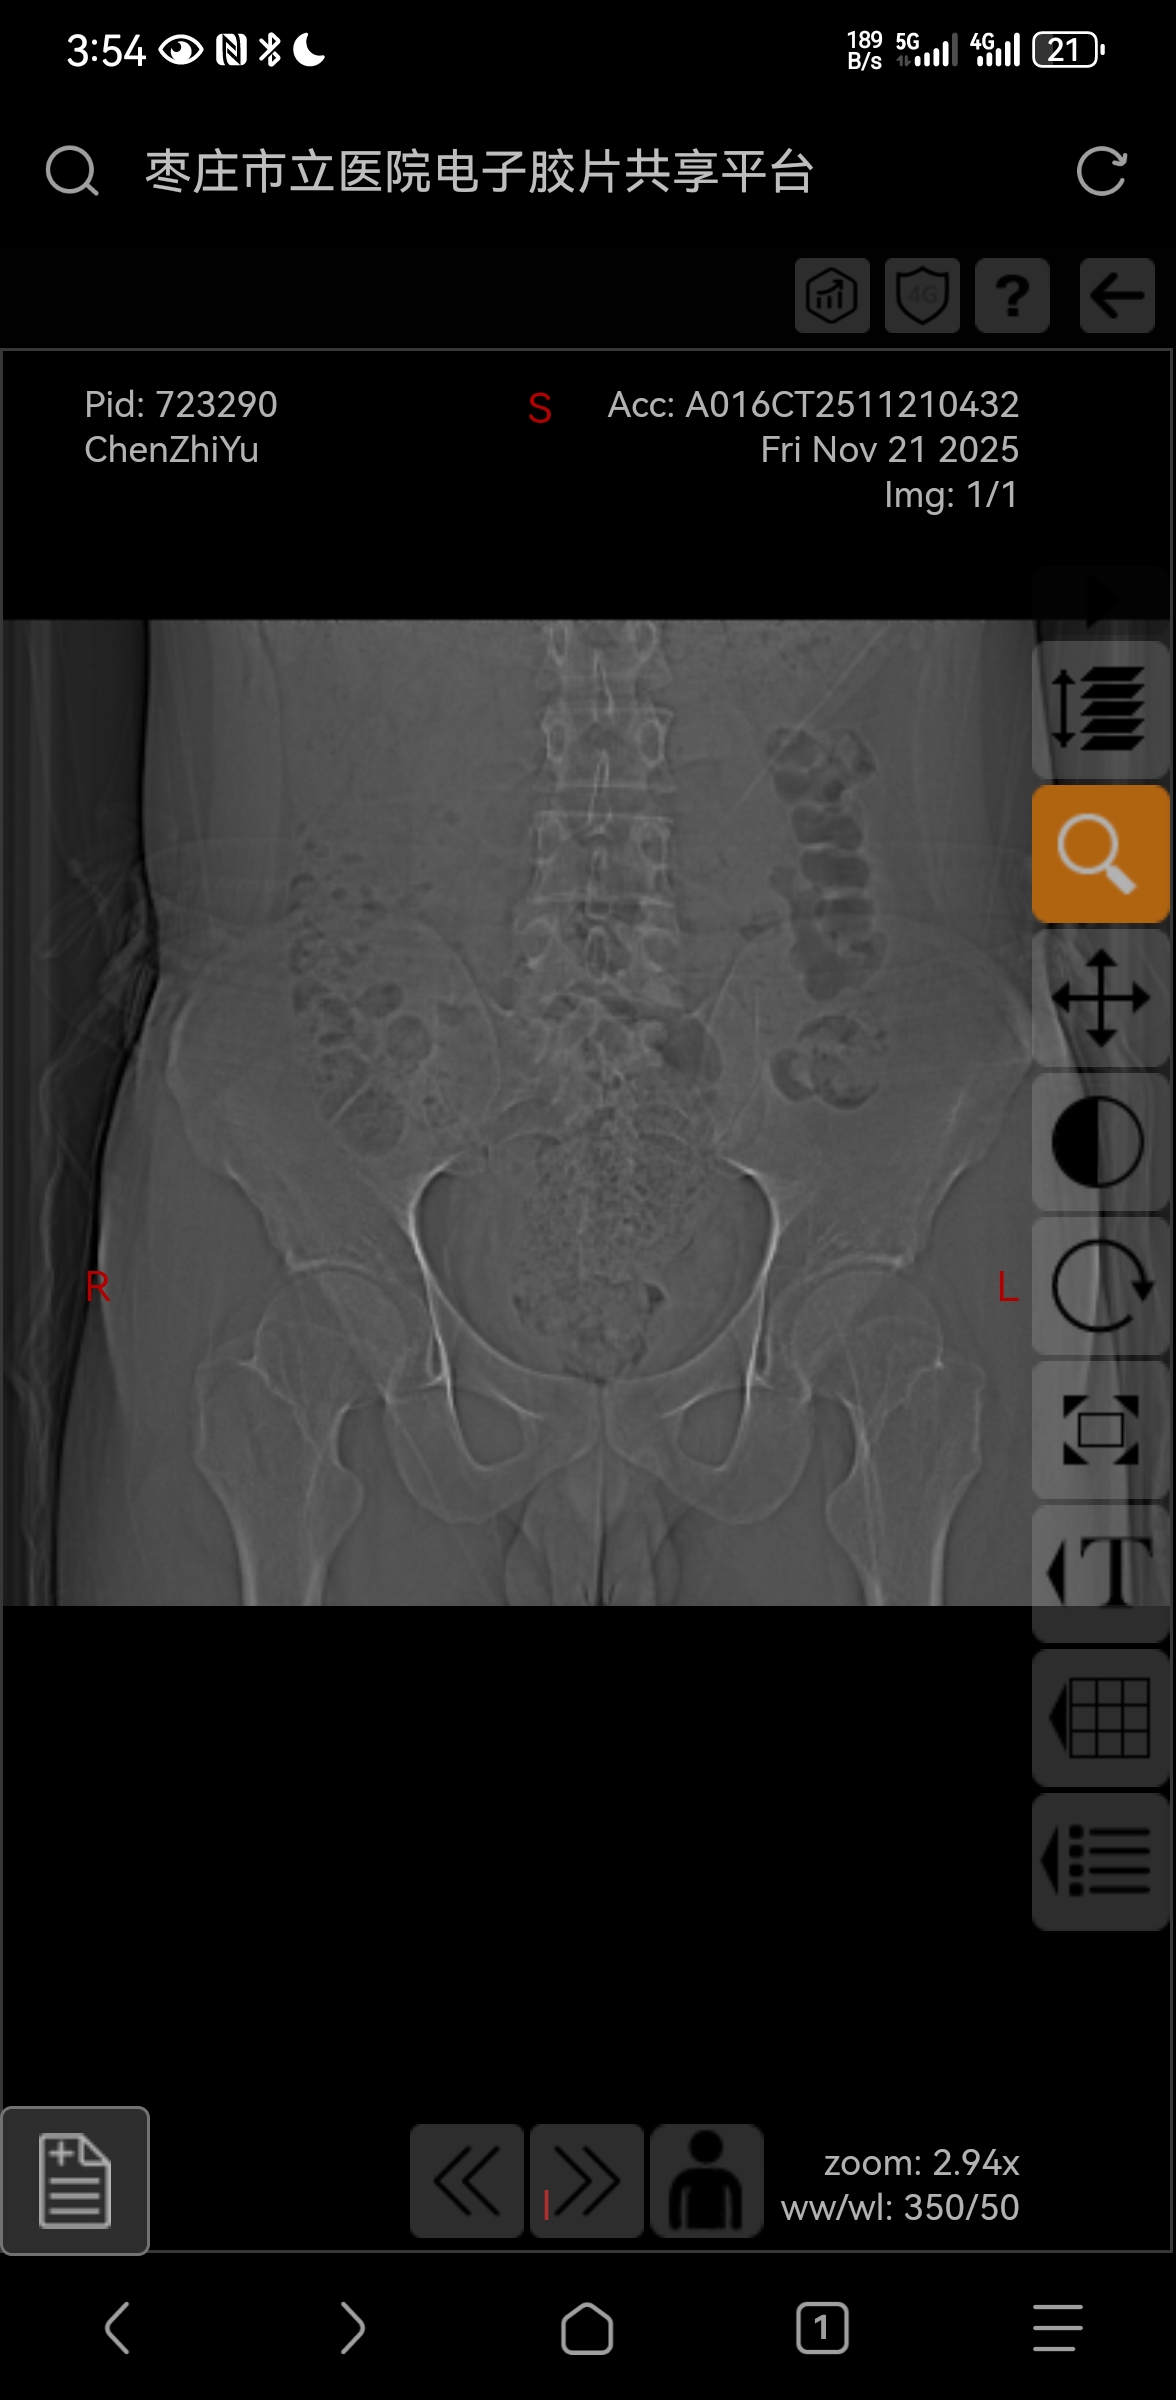

>>No.67476012

阴性,吃了五天的依托考昔了,睡觉的疼痛得到了很大的环节,但是坐着时左侧坐骨结节处还是不得劲( ´_ゝ`)

>>No.67504656

我咋感觉有点歪呢( ゚∀。)

>>No.67504714

不是错觉,确实有( ゚ 3゚)

哎呀临床上这样的多了去了,放宽心( ゚ 3゚)

这样,康复科/针灸推拿科请( ゚ 3゚)

无标题 无名氏 2025-11-26(三)16:59:00 ID:NUYUEbA [举报] No.67511698 管理

挂了肩颈腰腿疼痛康复科开了六次理疗,我问医生我这个是不是有点歪,他说确实歪,但是一种保护性的,我就问他我还需要推拿吗?他说不需要,希望理疗可以有效果( ´_ゝ`)